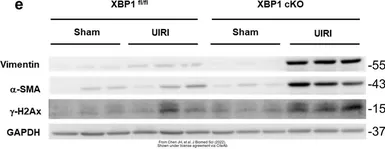

The data was published in the journal Front Pharmacol in 2016. PMID: 27199755